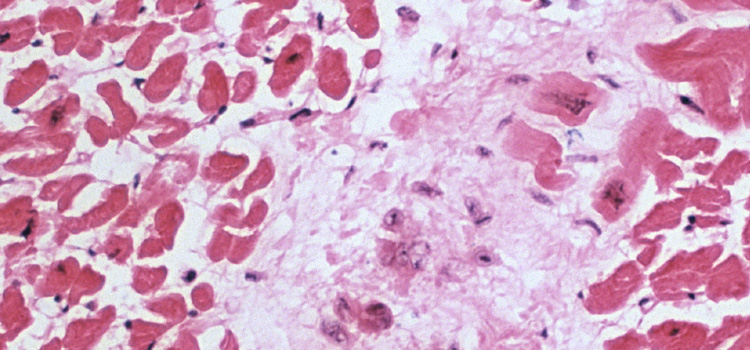

Las enfermedades reumáticas, el coste de la supervivencia durante la Pequeña Edad de Hielo

Una investigación del grupo de Biología Evolutiva Humana de la UPV/EHU da pistas sobre la prevalencia de cierto perfil genético en la población europea